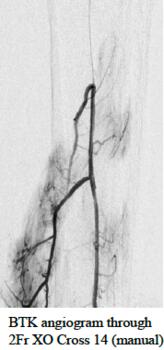

“The XO Cross devices deliver unique performance and control that make them an excellent tool for crossing above- and below-the-knee lesions,” said Dr. Jihad Mustapha, interventional cardiologist at Advanced Cardiac & Vascular Center in Grand Rapids, Michigan, USA. “The non-tapered XO Cross shaft, lubricious coating, low crossing profile, and 1:1 torque response will be critical for workhorse performance and reducing the need for wire escalation techniques in CLI cases.”

The unique XO Cross platform includes a metal-alloy exoskeleton, non-tapered shaft, proprietary hydrophilic lubricious coating, and large inner lumen for improved 1:1 torque, low-profile, pushability, tracking, crossing, fatigue-resistance, and angiography. XO Cross microcatheters have been safely and successfully used in challenging peripheral lesions above-the- including but not limited to above-the-knee and below-the-knee CTOs from contralateral femoral, antegrade femoral, and retrograde pedal access.

This 510k clearance includes new 2Fr XO Cross 14 Microcatheters, 2.6Fr XO Cross 18 Microcatheters, and 3.8Fr XO Cross 35 Support Catheters for use with standard 0.014”, 0.018”, and 0.035” guidewires in 90cm, 135cm, 150cm, and 175cm working lengths. The shorter 90cm devices support retrograde pedal and antegrade femoral access while the longer 175cm devices were designed specifically for radial access to peripheral use.